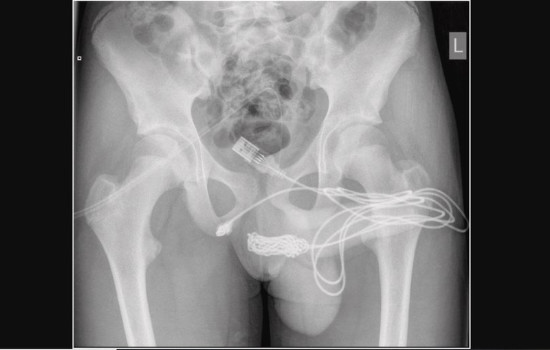

Imagem radiográfica pélvica simples do menino de 15 anos.(Foto: Reprodução)

Um garoto de 15 anos ficou com um cabo USB preso no pênis enquanto tentava medir o membro. O adolescente precisou realizar uma cirurgia para remover o fio eletrônico da uretra. O caso ocorreu em Londres, na Inglaterra e a identidade do menino não foi divulgada.

O incidente foi relatado pela revista científica “Urology Case Reports”. O periódico conta que o menino tentou retirar o cabo sozinho, mas acabou ficando com “as duas pontas penduradas em seu membro”. Após urinar sangue, ele procurou os médicos.

A família o levou a um hospital que o encaminhou para o University College Hospital London, para um melhor tratamento. No local, ele necessitou de avaliação urológica terciária urgente e tratamento cirúrgico aberto. Para retirar o cabo USB, foi realizada uma uretrostomia penoescrotal, que é um corte entre a genitália e o ânus do adolescente.

Ainda, segundo o papper, o cabo estava com nós e foi revelado na face proximal da uretra peniana e cortado do restante do cordão. Ambas as pontas do fio foram puxadas com sucesso. Após a cirurgia, o menino recebeu alta no dia seguinte com analgesia simples, antibióticos orais e cateteres suprapúbicos, para a drenagem da urina.